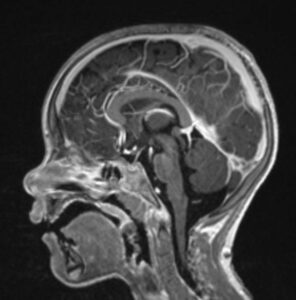

MRT-Untersuchungen: alle Körperregionen im Überblick

Die Magnetresonanztomographie (MRT) ist ein hochpräzises, nicht-invasives Verfahren der modernen Radiologie, das ohne Röntgenstrahlen auskommt. Sie ermöglicht detaillierte Einblicke in Organe, Gelenke, Nerven und Weichteile – angepasst an die jeweilige medizinische Fragestellung.

Der Ablauf einer MRT-Untersuchung ist klar strukturiert und ruhig. Individuell angepasste Protokolle, präzise Positionierung und moderne Sequenzen sorgen für eine hohe Bildqualität und verlässliche diagnostische Aussagen – unabhängig davon, ob Kopf, Wirbelsäule, Organe oder Gelenke untersucht werden.

MRT-Untersuchungen nach Körperregion